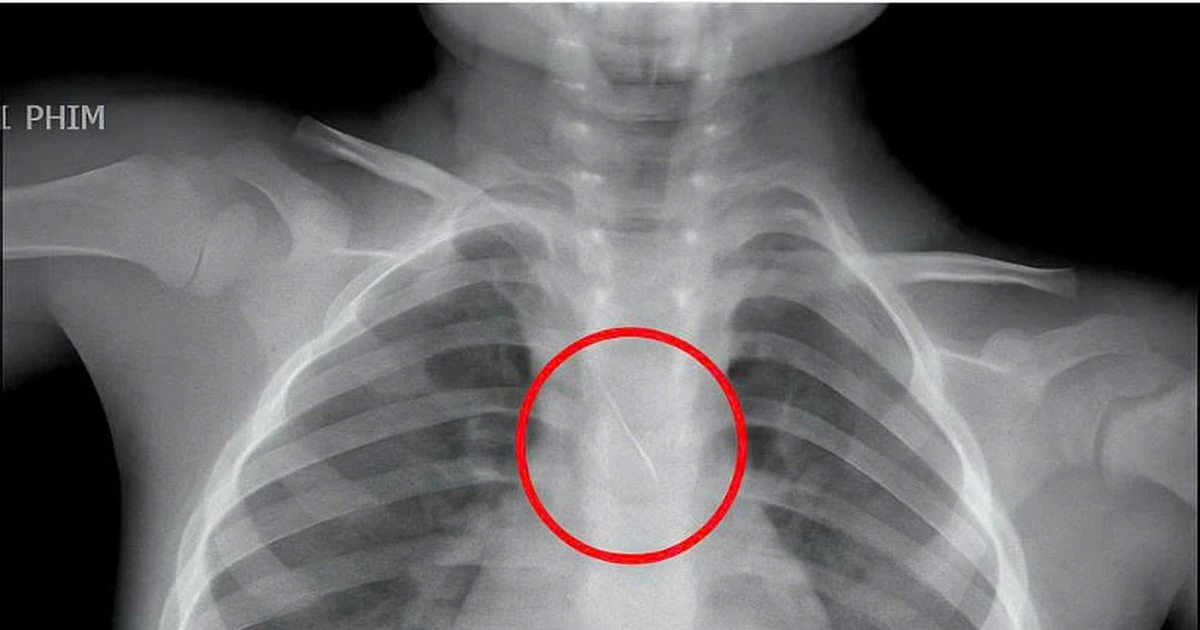

Đi làm răng, kim chọc tủy dài 22 mm 'cắm' vào đường thở bé trai 3 tuổi

Các y bác sĩ tại Bệnh viện đa khoa tỉnh Quảng Trị vừa gắp thành công một dị vật bị mắc kẹt trong khí quản của bé trai 3 tuổi.

Kim chọc tủy dài 22mm rơi vào đường thở bé trai 3 tuổi khi làm răng

Bé trai nhập viện trong tình trạng ho sặc dữ dội, được xác định hóc kim chọc tủy dài 22mm rơi vào đường thở khi đang làm răng.